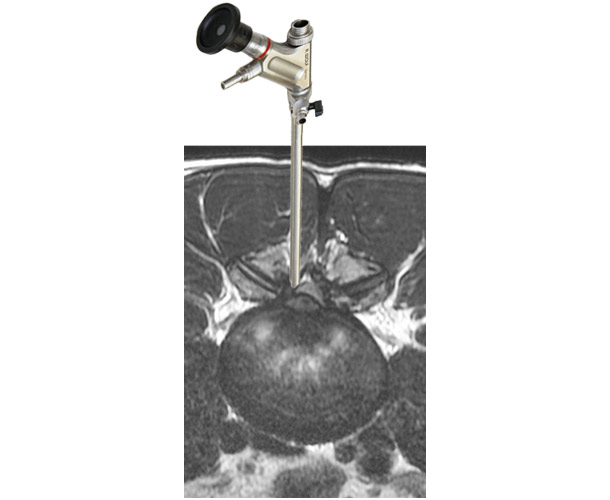

手術ナビゲーションシステムとは

せぼねの手術で用いられるナビゲーションシステムは、手術を安全に行うための機器になります。せぼねの病気はさまざまあり、患者さんによって病気の部位や骨の変形は異なります。また、せぼねの周りには大事な神経組織や血管が位置しているため、これらを傷つけないように手術が行われる必要があります。これまでは透視装置などを駆使して手術が行われていました。しかし、固定術で施行されるスクリューの誤設置や固定材料の不適切な設置がなされる場合がありました。

当院では様々な種類のナビゲーションシステムを採用しています。そのため、手術はより安全に行われ、手術時間の短縮、出血量の低減、被爆量の減少、さらには早期復帰につながるものと考えています。

ナビゲーションシステムを用いた

内視鏡手術

ナビゲーションシステムを用いた内視鏡手術

スクリューを用いた手術

ナビゲーションシステムを用いたスクリューを用いた手術